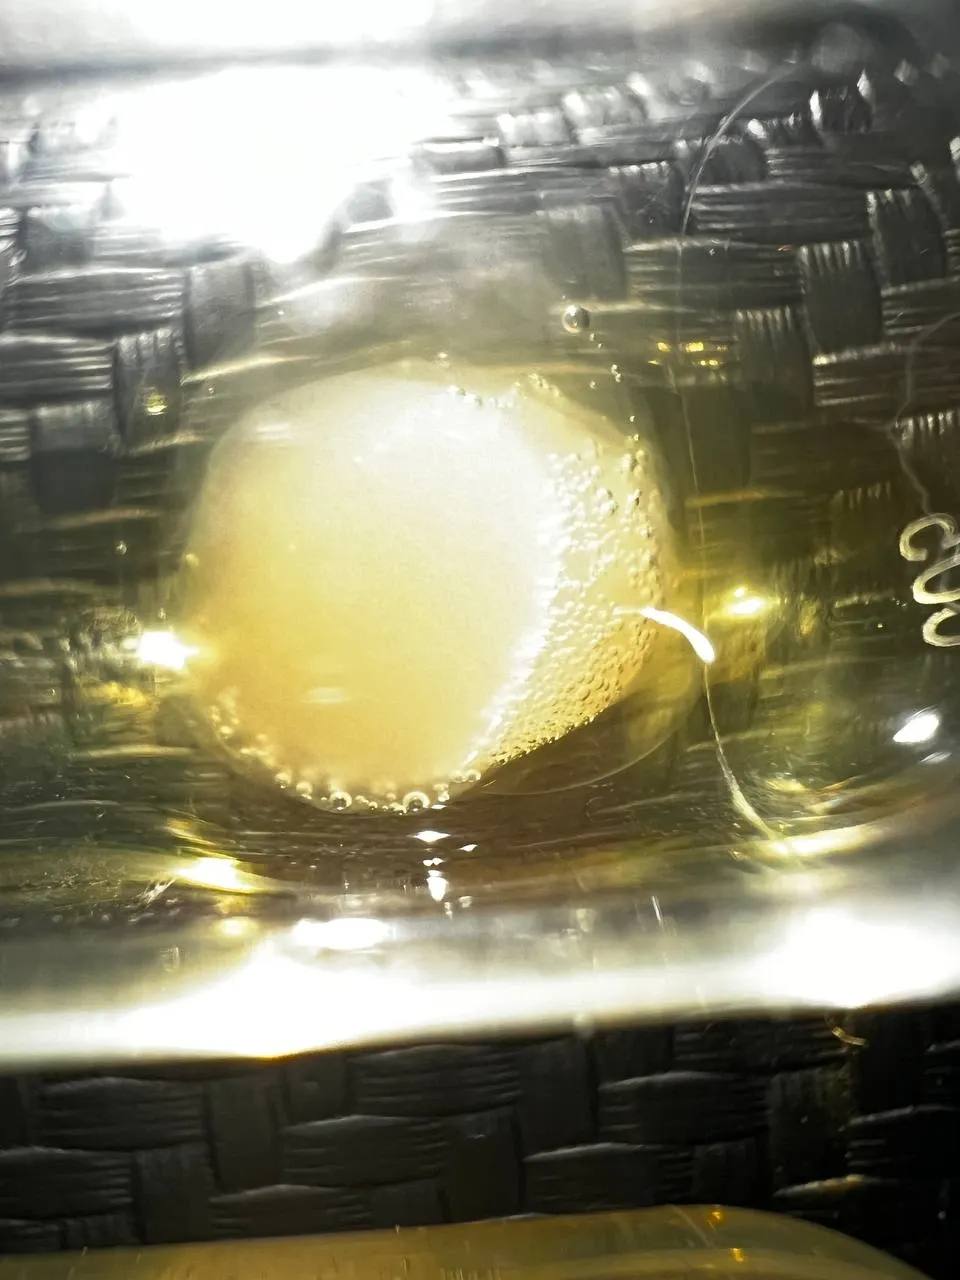

Галерея исследования

Результаты покадровой 4K съёмки образцов плазмы крови: пробирки, колбы и микроскопические снимки процесса коагуляции.